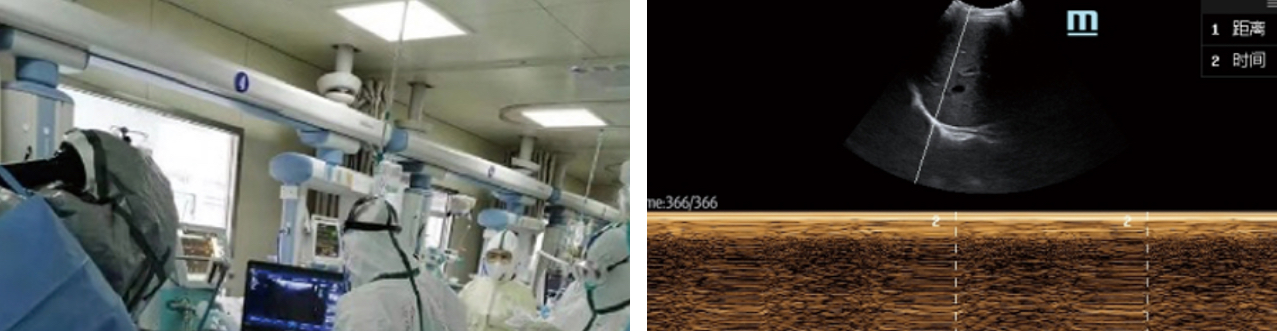

- 2. Para ventilaciĂłn mecĂĄnica, mida el lĂmite del diĂĄmetro de la vĂa aĂ©rea y seleccione el diĂĄmetro del tubo de ventilaciĂłn apropiado; observe el movimiento del diafragma y guĂe el ventilador fuera de lĂnea

- 2. Consulta remota, capacitaciĂłn y ense?anza